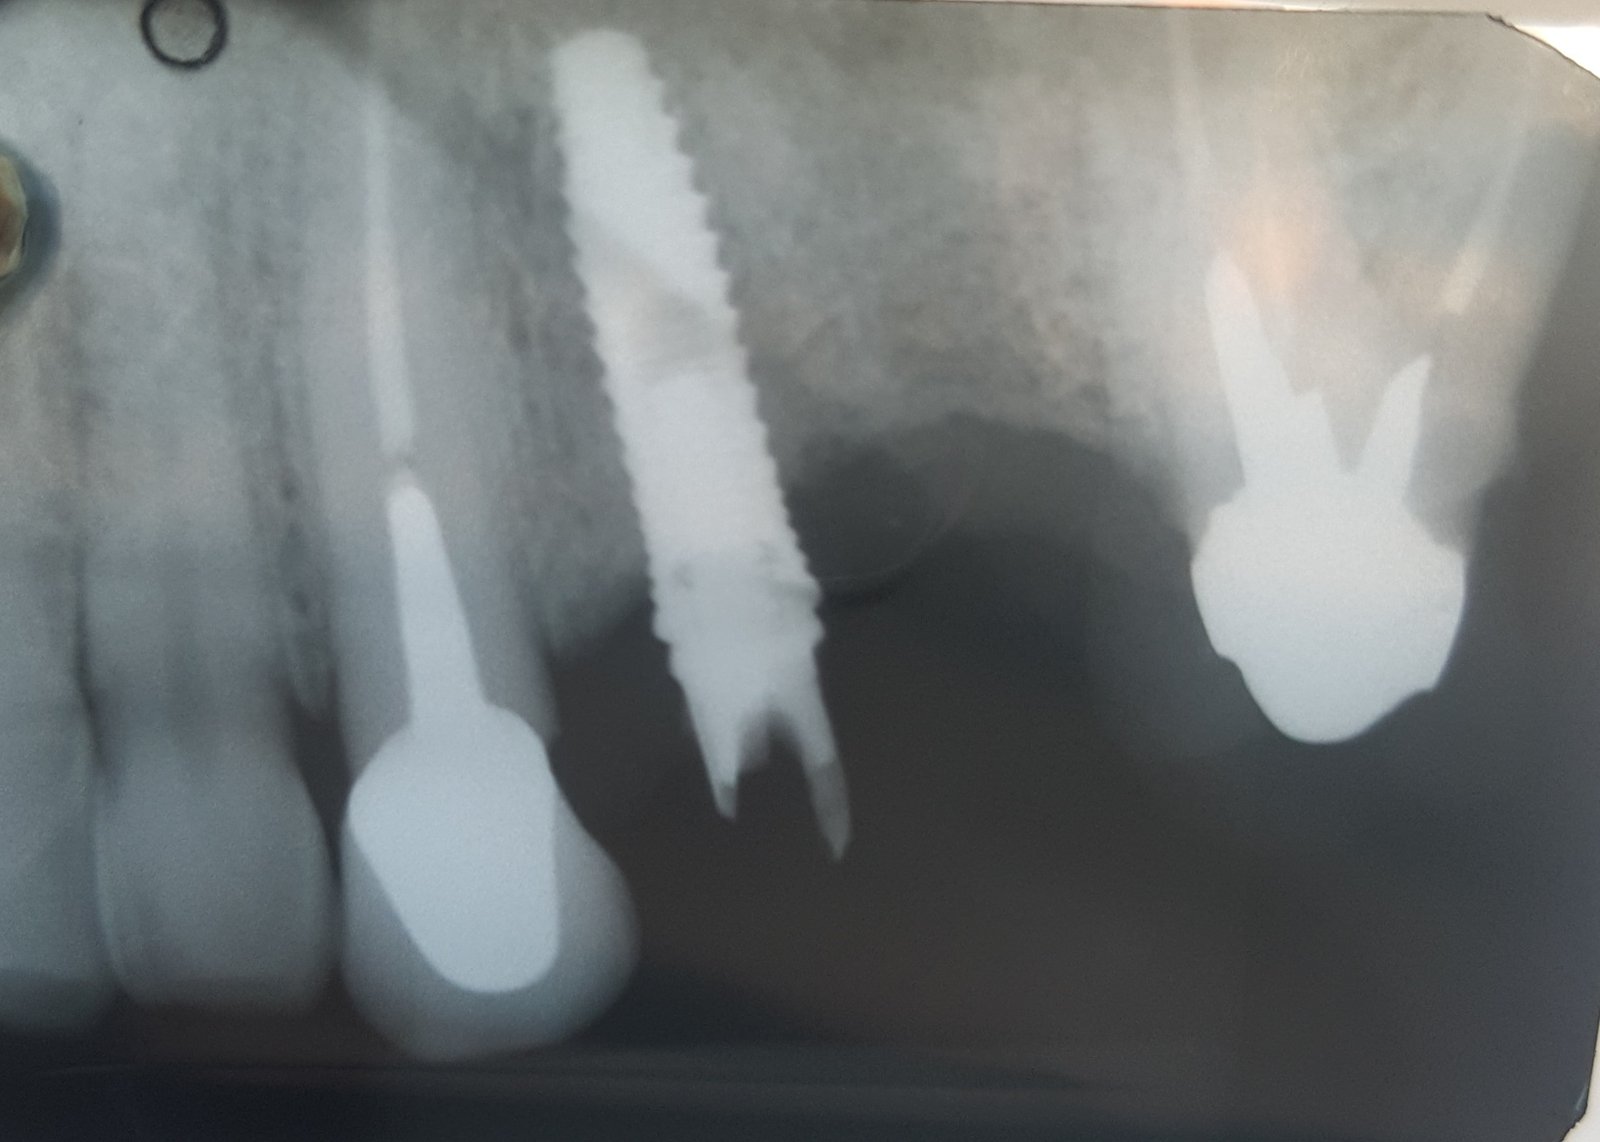

Buenas tardes! Paciente que viene con corona floja, era cementada y um compañero intentando apretar el tornillo del pilar ( que se había aflojado) fresó la cabeza del tornillo. Necesito [...]